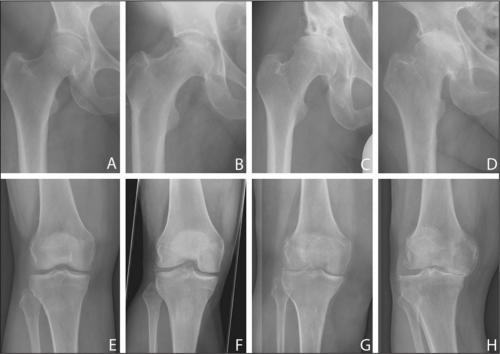

Стадии артроза коленного сустава. Обратите внимание на сужение суставной щели.